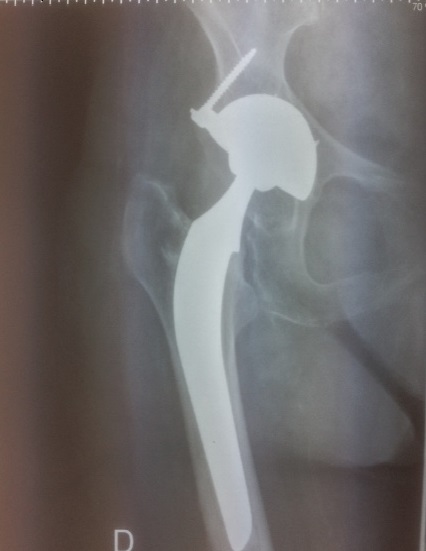

Dr Cottias - Opération / hanche Fracture du col fémoral : Ostéosynthèse et prothèse de hanche

Fracture du col fémoral : Ostéosynthèse et prothèse de hanche

Une incision est réalisée à la face antérieure, externe ou postérieure de la hanche et de taille adaptée selon les cas (entre 8 à 20 cm), éventuellement sur table orthopédique (traction au pied ou fémorale). Une ostéosynthèse (vis, vis plaque, clou-plaque, clou centromédullaire avec vis cervicale) est réalisée pour les cas de fracture sous capitale non déplacée et avec un capital osseux suffisant ou les fractures per-trochantériennes. Une prothèse de hanche totale, à cupule mobile ou cervico-céphalique est posée pour les fractures sous capitales à risque de nécrose ou certaines fractures basi-cervicales ou autres en cas de coxarthrose associée.

Après quelques jours d’hospitalisation, la sortie sera autorisée après contrôle radiologique pour vérifier la bonne position de la prothèse. La marche en général n’est plus douloureuse sauf en cas d’ostéosynthèse. Une rééducation de la marche et des postures sera poursuivie soit à domicile avec un kinésithérapeute soit en centre de rééducation.

PHOTOS :